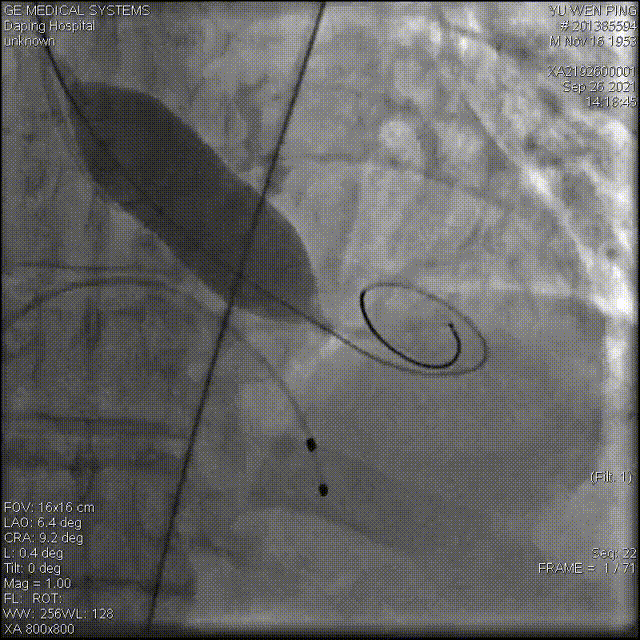

术中影像

以 Seldinger法穿刺右桡动脉,行PCI后,使用PIG造影管行主动脉根部造影

22mm球囊预扩

造影确定输送器位置

高位释放瓣膜

受钙化挤压影响,瓣膜展开状态差,决定进行后扩

22mm球囊后扩

经后扩,支架展开形态良好